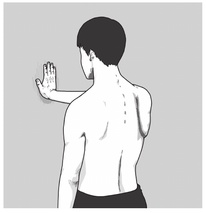

9

第60回 午前

|

作業療法士実地問題

32歳の男性。右上肢の筋力低下を訴えて受診し、理学療法が開始された。筋力を評価するために、右上肢を前方挙上して壁を押させた時の様子を図に示す。その結果、右肩甲骨の内側縁全体が胸郭から離れる現象が認められた。筋力低下が最も疑われる筋はどれか。

1

棘下筋

2

肩甲下筋

3

広背筋

4

前鋸筋

5

大円筋